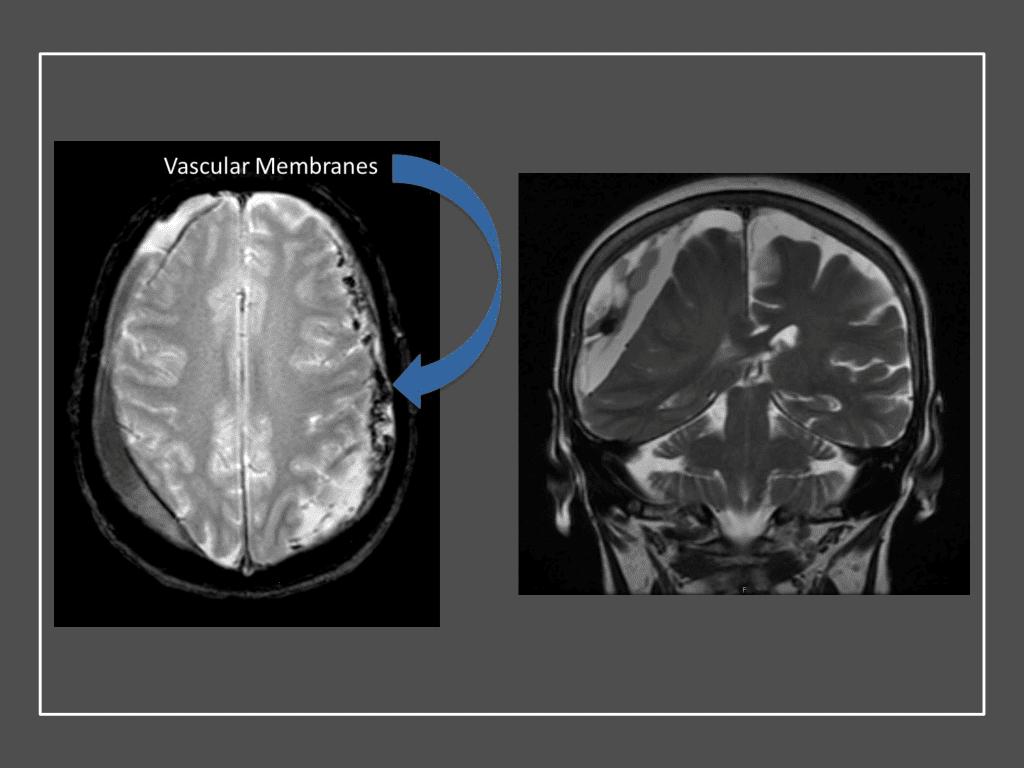

CT follow-up at 1 week demonstrates early resorption. 2 weeks post MMA embolization, resolution of the left subdural collection with new small thin acute hemorrhage in an otherwise stable right subdural collection is observed (Figure 3. A and B).

Figure 3. A) 1 week post MMA embolization demonstrating decreasing thickness bilaterally B) 2 weeks post MMA demonstrates resolution on left, with small new acute component on right with overall decreased thickness.

Clinically, the patient improved over the few weeks with the occasional transient twinge of a headache, but resolution of dizziness. Follow-up CT at 10 weeks demonstrated complete resolution of the bilateral subdural hematomas with our patient completely asymptomatic and back to all of her activities of daily living. Considering her history of thrombocytopenia and CLL, we will continue to monitor her into the future and are excited about her progress and recovery. (Figure 4. A and B)

Figure 4. A and B) – 10 weeks following embolization demonstrates complete resolution of bilateral collections both acute and chronic.